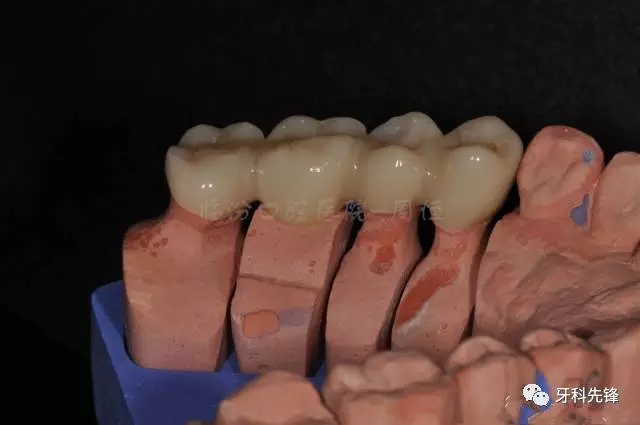

圖22烤瓷冠咬頜照

640.webp (26).jpg